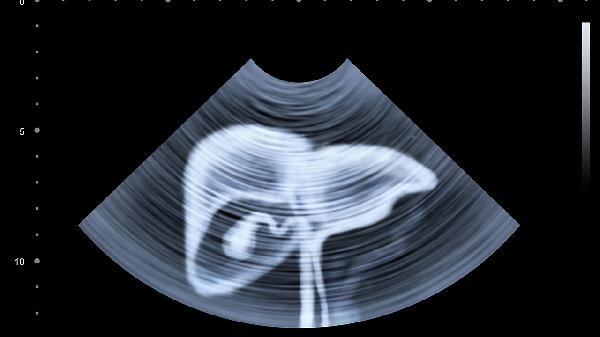

3、蜘蛛痣

中心红点周围辐射状毛细血管扩张,形似蜘蛛。常见于面部、颈部,与雌激素水平变化有关,像皮肤上的"小太阳"。